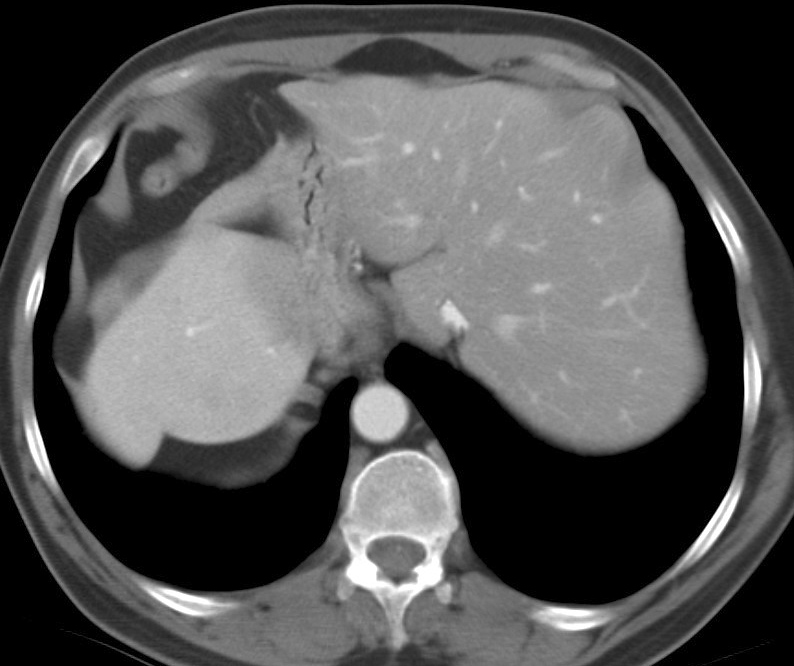

Gallery Congenital For Morgagni Ex 1 CT (b)

For Morgagni

Ex 1 CT (b)